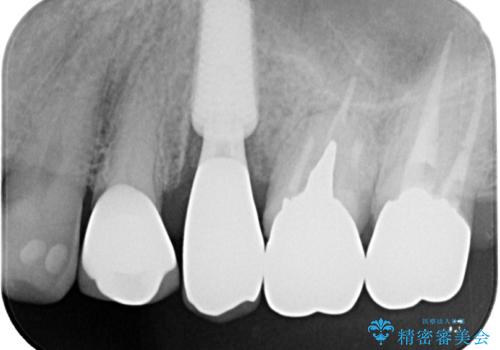

抜歯即時埋入後にはずっと気になっていた排膿が消え、痛みも腫れも特になく、3ヶ月という短期間で無事に治療を終えることができました。

破折した奥歯 抜歯即時埋入インプラントによる補綴治療